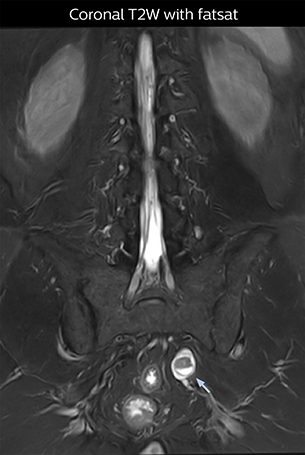

“The intra-luminal signal of veins, especially around the intervertebral space, can be suppressed well with NerveVIEW. As a result, we can easily observe the detailed nerve structure around the posterior ganglion,” he says. “This is why we use 3D NerveVIEW for intraforaminal stenosis and extraforaminal stenosis/herniation (lateral disc herniation). On the other hand, if herniation is suspected to exist inside the dorsal root ganglion (DRG), balanced TFE or ProSet-FFE is applied. NerveVIEW is not suitable for evaluating the median type of herniation.” The SE-EPI DWI-based method for MR neurography works well for large FOV exams like whole-body MRI, but focal examination of nerves is often limited by the attainable spatial resolution (both inplane and slice direction) and geometric distortion. “3D NerveVIEW achieves higher in-plane resolution – close to our other routine spine sequences – and the source images can be used instead of adding a fat-suppressed T2-weighted sequence,” Tanji says.

According to Tanji, methods such as ProSet FFE, STIR or 3D VISTA are anatomically nonselective because background signals, for instance from blood vessels, often interfere with nerves, which hampers evaluation of details, especially at the peripheral side of the nerves.